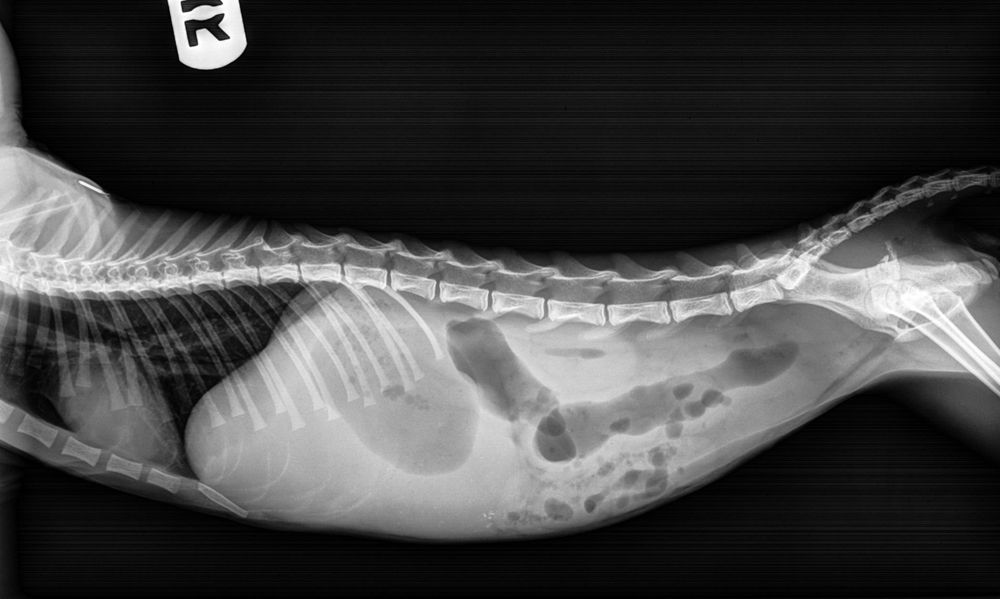

But it soon became clear the little cat was suffering terribly with severe constipation, prompting her to take him for X rays of his colon, after which vets told Ginevra her 'Tom' cat looked more like a queen – leading her to rename the animal Garie-Ann.

But when, within a few days, he became worryingly constipated, she feared he had a condition called megacolon – an abnormal dilation of the large intestine.

Taking him with her to work, her colleagues performed another X ray, revealing that he was seriously constipated once again.